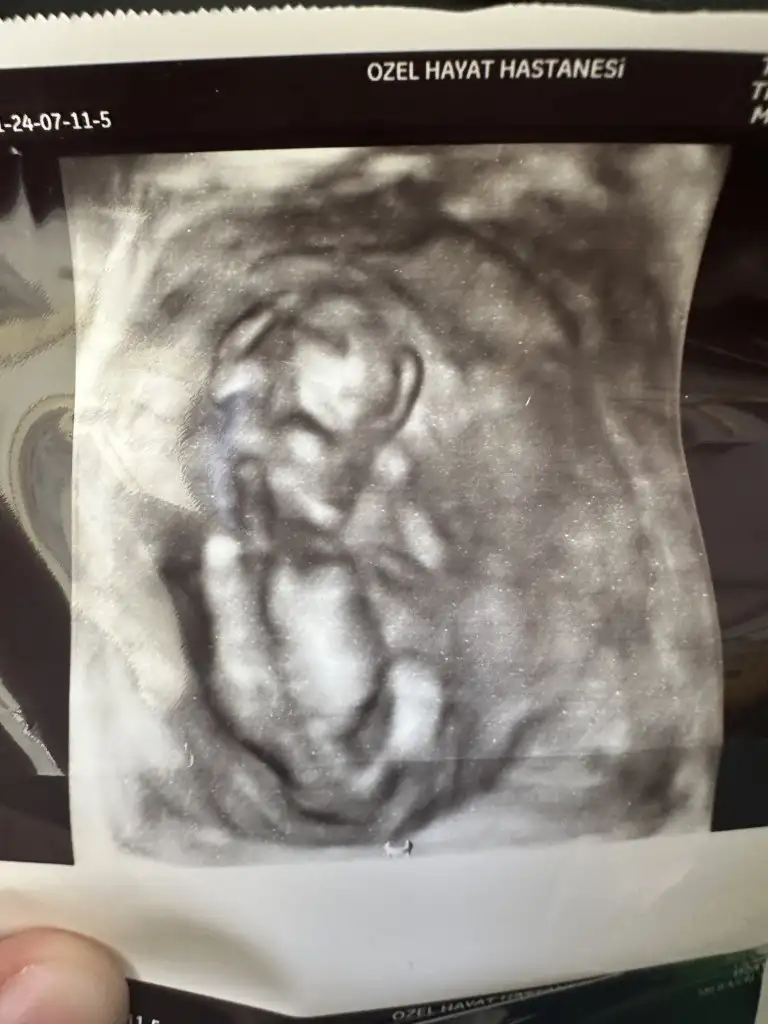

Merhaba biz de 12 haftalığız ultrason resim çok benzettim benim bebeğime bize doktor yanılma payım yüksek emin değilim sadece tahmin kıza benziyor dedi sizce bakar mısınız kız mı erkek mi bana hiç kız gibi gelmiyor erkek gibi geliyor

Doktor bacak arası resim verdi sizce nedir cinsiyeti

Kızlar dün doktorum cinsiyet tahmini yaptı kız büyük ihtimal ama 3 hafta sonra tekrar bakarız kesin o zaman belli olur dedi ben hep erkek hissediyordum ama kız olunca çok mutlu oldum hissiyat olarak sadece erkek olucak kesin diyordum ama yanıldım sanırım sizce cinsiyeti değişicek mi çok heycanlıyım ☺️ Ultrason fotoğrafını asağıya ekliyorum Eki Görüntüle 3233482